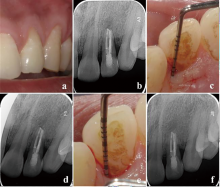

显微根管治疗结合意向性牙再植术治疗双根管上颌侧切牙畸形根面沟1例

Microscopic root canal therapy combined with intentional replantation for the treatment of palatogingival groove in the maxillary lateral incisor with two root canals: A case report

畸形根面沟(palatogingival groove,PGG)是一种位于根面的发育性解剖异常,多见于上颌侧切牙。PGG处牙周组织附着薄弱,易滞留菌斑,引起局部牙周炎症,感染可通过根面沟扩散至牙髓组织,最终导致牙周牙髓联合病变。本文报道了1例因畸形根面沟引起的左上颌侧切牙牙周牙髓联合病变,经显微根管治疗联合意向性牙再植术成功保留患牙,并进行文献回顾,探讨了PGG的诊断要点及治疗方案。

Palatogingival groove (PGG) is a developmental anatomical defect located on the lingual root surface, frequently observed in maxillary lateral incisors. The periodontal attachment in this region is delicate, which makes it vulnerable to plaque accumulation and increases the risk of periodontal inflammation, leading to combined periodontal-endodontic lesions. This article reports a case of a combined periodontal-endodontic lesion in a left maxillary lateral incisor caused by PGG. The tooth was successfully preserved through microscopic root canal therapy combined with intentional replantation. Additionally, a literature review was performed to highlight the key diagnostic features and treatment strategies for PGG.